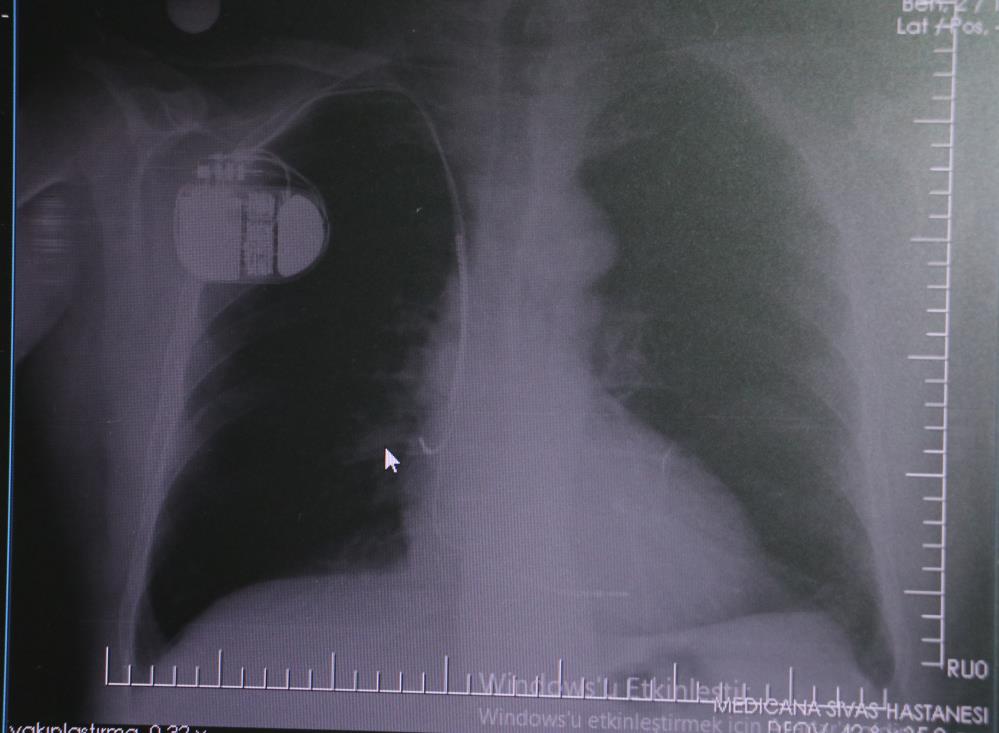

Sivas Medicana Hastanesi Kardiyoloji Uzmanı Dr. İsmail Erdoğu, kalp pili tedavisinin ani ölümleri önlemede büyük rol oynadığını belirterek, özellikle soğuk havalarda kalp pili kullanan hastaların dikkatli olması gerektiğini söyledi.

Dr. Erdoğu, kalp pilinin önemine dikkat çekerek, yeni nesil kalp pillerinin MR cihazlarına girmeye uygun olduğunu ancak tarama cihazlarından geçilmemesi gerektiğini belirtti. “Soğuk hava nedeniyle oluşan titremeler, kalp pilinin kalbin durduğunu sanmasına ve yanlış şoklamaya yol açabilir. Bu nedenle hastalarımızın bu dönemlerde daha dikkatli olmalarını öneriyoruz” dedi.

Kalp krizleri sonrası kalpte oluşan hasarın uzun vadede ritim bozuklukları ve ani ölümlere yol açabileceğini söyleyen Erdoğu, “Kalp pilleri, uygun hastalarda ani ölümleri engelliyor. İnsanlar bir şokla hayata tutunurken, pil olmasaydı öleceğini düşündüğümüz birçok hastamız var. Soğuk havalarda vücutta oluşan titremeler, kalp pilinin hafızasını karıştırıp gereksiz şoklamaya yol açabilir. Bu nedenle bu dönemde temkinli olunmalı” diye konuştu.